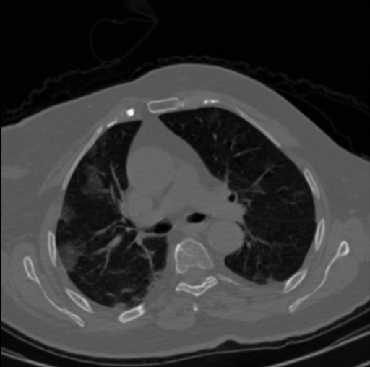

Early and reliable COVID-19 diagnosis based on chest 3-D CT scans can assist medical specialists in vital circumstances. Deep learning methodologies constitute a main approach for chest CT scan analysis and disease prediction. However, large annotated databases are necessary for developing deep learning models that are able to provide COVID-19 diagnosis across various medical environments in different countries. Due to privacy issues, publicly available COVID-19 CT datasets are highly difficult to obtain, which hinders the research and development of AI-enabled diagnosis methods of COVID-19 based on CT scans. In this paper we present the COV19-CT-DB database which is annotated for COVID-19, consisting of about 5,000 3-D CT scans, We have split the database in training, validation and test datasets. The former two datasets can be used for training and validation of machine learning models, while the latter will be used for evaluation of the developed models. We also present a deep learning approach, based on a CNN-RNN network and report its performance on the COVID19-CT-DB database.